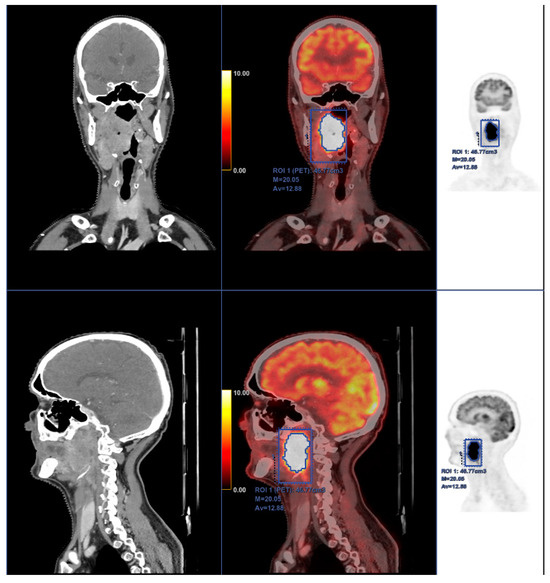

Dr Sue Cancer Vet - 💙SPOTLIGHT ON CANINE LYMPHOMA。Meet Dr. Catherine Rebholtz, Citrus Heights Medical Director。PET Imaging of Differentiated Thyroid Cancer with TSHR。VETERINARY ONCOLOGY No.47※裁断済みです。【特集】日常でよく遭遇する厄介な腫瘍を克服しよう内分泌腫瘍~犬と猫の副腎・甲状腺!●監修にあたって/瀬戸口明日香●内分泌腫瘍の病理学的診断/近藤広孝●犬の副腎腫瘍 外科治療/金 尚昊 ●犬の副腎腫瘍 放射線治療/細谷謙次●猫の副腎腫瘍/奥 朋哉●犬と猫の甲状腺腫瘍/岩田泰介●インスリノーマ/細谷謙次●グルカゴノーマ/原田 慶●ガストリノーマ/阪本恵美●カルチノイド/佐藤慶太●下垂体腫瘍 放射線治療/吉川陽人●下垂体腫瘍 内科治療/佐藤佳苗●ケモデクトーマ 放射線治療/塩満啓二郎●ケモデクトーマ 内科治療/永浦香里●上皮小体腫瘍/市川美佳【連載】●こちらエキゾチックペットの腫瘍科 第12回フクロモモンガ(Petaurus breviceps )に認められた乳腺癌の2例/山下智之※公式サイトより引用一部ページの端にヨレや折れ目が少しありますが、内容には影響しない程度かと思います。ページの欠落はありません。素人保管の中古品ですので、神経質な方はご遠慮ください。通常、1週間以内に発送いたします。獣医学雑誌を他にも出品しておりますので、おまとめ買いなどお気軽にご相談ください。#獣医 #教科書 #雑誌#EDUWARDPress。Unexpected Clinical and Laboratory Observations During and。【裁断済み】胸部のCT 第4版。神経局在診断 第6版。【裁断済】卒後20年目総合内科医の診断術 ver.3。UP TO DATE 2024・2025 診療ガイドライン。改訂2版 超入門 形成外科・美容外科手術 (裁断済み)